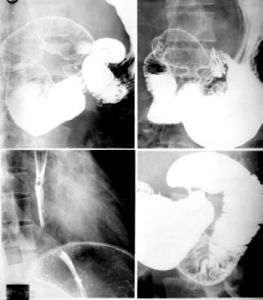

2.X線檢查

(1)腹部平片:採取仰臥、直立或側臥位腹部平片,可排除腸梗阻和腸穿孔對新生兒小腸扭轉壞死性腸炎及胎糞性腹膜炎尤為重要。

(2)鋇劑造影:稀鋇餐在非急性出血期造影是有一定價值的,常常加甲基纖維素作雙層對比。也可在十二指腸插管後注入鋇劑作小腸造影檢查(加或不加甲基纖維素)。鋇灌腸常有助於腸套疊之診斷。